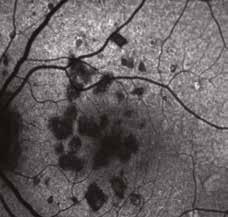

Nel corso del follow-up di tali pazienti si verificava spesso, come ben evidenziato dall’imaging in auto-fluorescenza (AF) nel tempo, un rapido e significativo incremento delle aree atrofiche, solo pochi mesi dopo la sostituzione del DHA algale dall’integratore Areds2 con olio di Krill, cosa mai avvenuta nel precedente lungo follow-up dei medesimi pazienti durante integrazione con DHA algale. (Fig. 2)

Fig. 1. Imaging infrarosso ed OCT mostra un Rapido ed insolito appianamento di ampio distacco dell’EPR maculare in DMS in donna di 75 aa, con significativo miglioramento visivo da 0.6 logmar a 0.1 logmar e nell’integrità delle linee recettoriale nella zona ellissoide, in particolare in assenza di aree atrofiche successive al riassorbimento.

Baseline: notare chiazze biancastre segno di sofferenza EPR

18 mos dopo formula areds2 & DHA Algale: chiazze tondeggianti scomparse

9 mos dopo rimozione DHA algale dalla formula Areds2

Fig. 2. Notare che nei 18 mesi di integrazione l’auto-fluorescenza della macula della paziente di 78 aa con AMD rimane libera da significative aree atrofiche, fintanto che il paziente continua ad assumere la formula antiox AREDS2 arricchita di olio algale, mentre solo 9 mesi dopo la sostituzione del DHA algale con DHA da pesce Krill, si osserva la rapida comparsa di significative ed invalidanti aree atrofiche a coinvolgere diffusamente l‘area maculare,altamente impattanti sull’acuità visiva della paziente fino a rendere estremamente difficoltosa la capacità di lettura, con un calo visivo fino a 2/10 da 8-9/10.